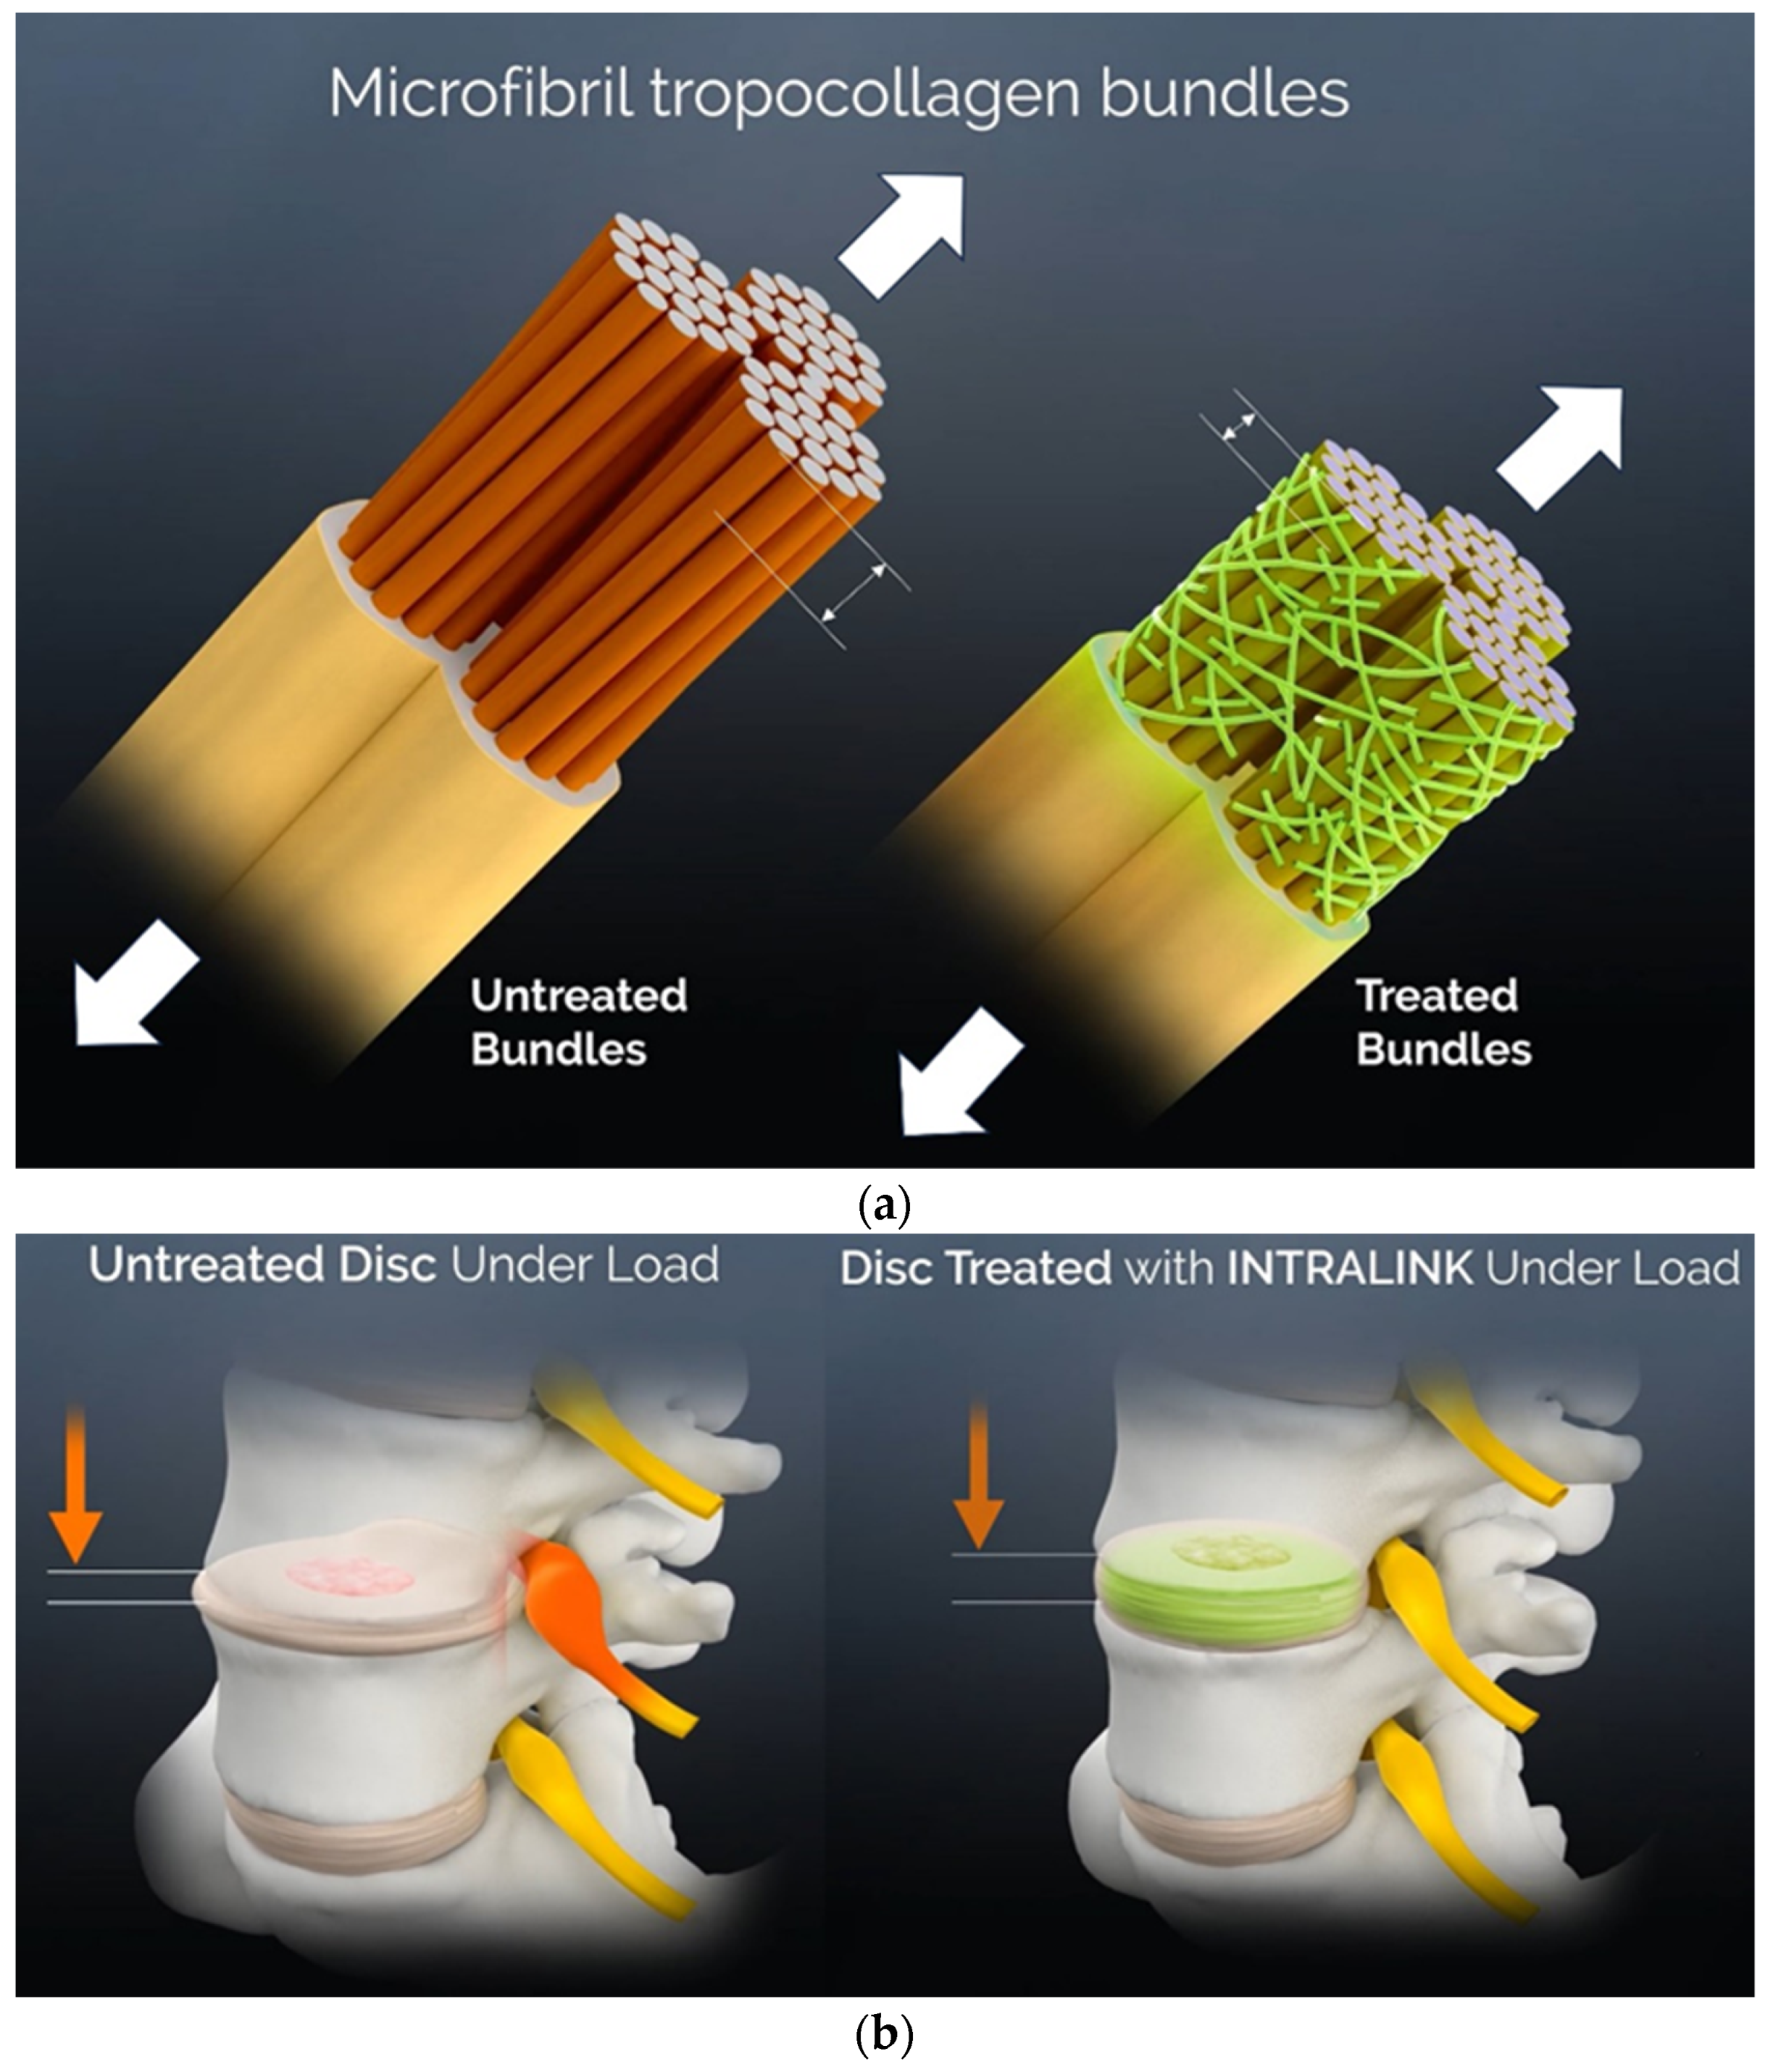

3.2. The Reaction Kinetics of Genipin in Collagenous Tissues

3.3. A Mechanical Effects Review

| Annulus mechanical properties such as tensile strength, yield strength, resilience and toughness [32,36,37] | 50% or more improvement |

| Disc bulging under a load [32,38] | 38% reduction |

| Resistance to tear propagation, delamination [39,40] | Up to 70% increase |

| Tensile stress levels in annulus [47] | 3- to 8-fold lower |

| Annular sealing, disc pressure restoration [49,50] | 5- to 7-fold increase |